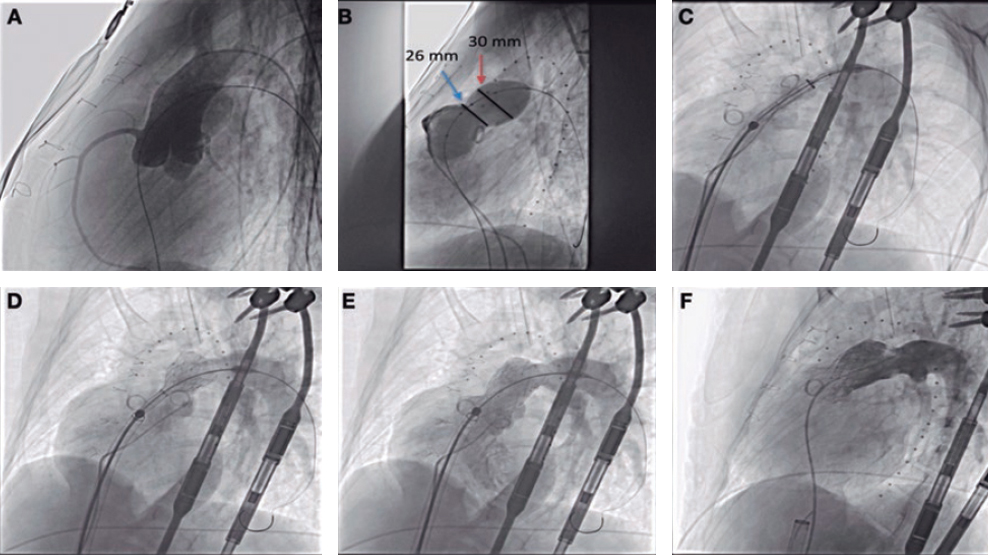

Afterwards we proceeded with the eventless advancement of a new zotarolimus-coated stent (Medtronic Resolute Onyx, 4 × 22 mm) towards the proximal segment by navigating inside the guiding catheter extension device (figure 3). This second stent was implanted and anchored to the previous one and adjusted to the ostium. It was dilated with high pressure with the delivery balloon including the visible segment protruding into the aorta in order to achieve the longitudinal shortening of the stent by overexpansion (figure 4).

Figure 3. Implantation of zotarolimus-coated stent in the proximal segment of right coronary artery.

Figure 4. Post-dilatation with balloon of the previous implanted stents especially of the portion protruding into the aorta in order to achieve the greatest possible longitudinal shortening.